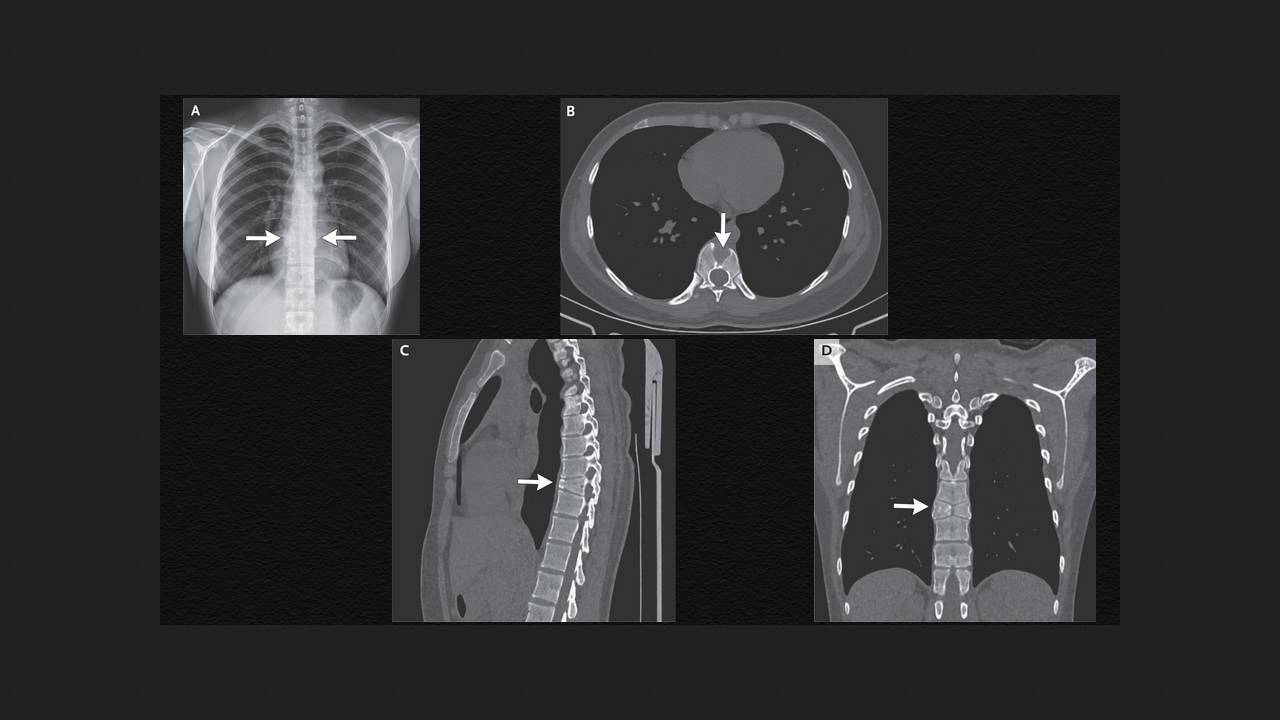

A 21-year-old woman presented to a Chinese pulmonology clinic with complaints of a week-long cough and sore throat. Examination revealed only moderate pharyngeal redness. She had no history of back pain. A chest X-ray revealed normal lungs and two hemivertebrae at the site of the ninth thoracic vertebral body. She was referred for a CT scan, which revealed sagittal clefting, anterior wedge deformity, and symmetrical triangular hemivertebrae at the level of the ninth thoracic vertebra. Shuai Ding and Xin Pan from the Fourth Affiliated Hospital of China Medical University in Shenyang shared this case in The New England Journal of Medicine.

Based on radiographic findings, the woman was diagnosed with a butterfly vertebra, a rare congenital anomaly caused by the failure of the two lateral ossification centers of the vertebra to fuse during fetal development. This defect can be isolated, as in this case, or combined with other developmental anomalies. Further examination by specialized specialists confirmed the benign nature of the condition and the absence of the need for specific treatment. The cough and sore throat were considered manifestations of an uncomplicated upper respiratory tract infection, and supportive therapy was prescribed.